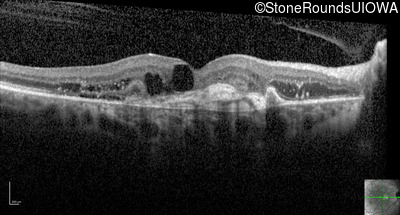

Optical Coherence Tomography - Right - 20/250

Exemplar / OCT Stack

Infrared Fundus Photograph - Right - 20/250

Exemplar